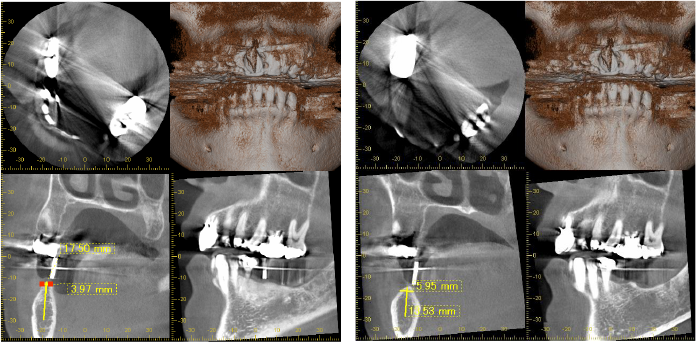

CT所見

ほぼ骨内には埋入できましたが、骨の厚みが足りないため、人工骨を移植し縫合しました。